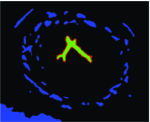

Appearance is one of the most important visual cues to distinguish between different structures in an image. Appearance is described by studying the distribution of different features such as intensity values in gray-scale images, color, and texture inside each object. In most cases, appearance models are incorporated into the data term in (2) and (7). The purpose of incorporating appearance prior is to fit the appearance distribution of the segmented objects to the distribution of objects of interest, e.g. using Gaussian mixture model (GMM) (Rother et al., 2004). In the literature, there are two ways to model the appearance: 1) adaptively learning the appearance during the segmentation procedure, and 2) knowing the appearance model prior to performing segmentation (e.g. by observing the appearance distribution of the training data). In the former case, the appearance model is learned as the segmentation is performed (Vese and Chan, 2002) (computed online). In the second case, it is assumed that the probability of each pixel belonging to particular label is known, i.e. if represents a particular set of feature values (e.g. intensity/color) associated with each image location for object, then it is assumed that is known (or pre-computed offline). This probability is usually learned and estimated from the distribution of features inside small samples of each object. Figure 9 illustrates the probability of different structures (the kidney, the tumour, and the background) in an endoscopic scene. A lower intensity in Figures 9(b-d) corresponds to higher probability.